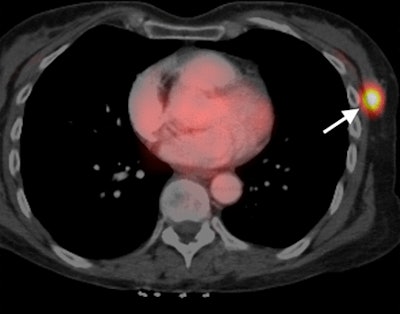

California researchers have found links between the appearance of triple-negative breast cancer on two different imaging modalities, MRI and PET/CT. They believe their findings can help guide therapy for the disease, which occurs less frequently but is typically more deadly than other types of breast cancer, according to a study published online July 22 in Radiology.

Researchers from the University of California, San Francisco (UCSF) found a strong association between dynamic contrast-enhanced (DCE) MRI signal enhancement ratio and maximum standardized uptake values (SUVmax) from PET/CT scans. The relationship could help illustrate the progression of triple-negative breast cancer and be a valuable tool to assess a patient's prognosis, they concluded.

FDG-PET/CT examinations were performed on a PET/CT system with a 16-slice CT device (Biograph 16, Siemens) or a 64-slice CT system (Discovery VCT, GE). Patients received 12.5 mCi (± 2.5 mCi) of FDG, with scans starting approximately 60 minutes (± 15 minutes) thereafter.

Patients were also given a 150-mL injection of iohexol (Omnipaque 350, GE) for the CT scans, with PET exams conducted in 3D mode with seven to 10 bed positions immediately after CT.

For SUV measurement, PET, CT, and fused PET/CT images had a region of interest placed over any FDG-avid breast focus by two radiologists who were blinded to MRI results and patients' pathologies.